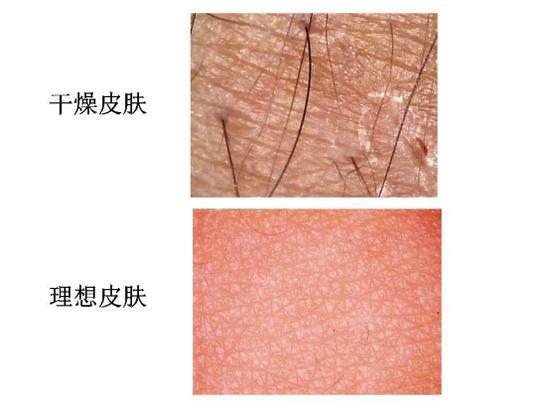

皮炎、湿疹和荨麻疹是最常见的皮肤病,有过敏导致的,有免疫力下降导致的,也有气候导致的,还有护理不当导致的。。。。。。。我遇到好几例这样的患者,顽固性湿疹,到冬天就发。来院面诊的时候发现,干性肤质,冬天的时候天天洗澡,而且用香皂洗得干干净净。我告诉她减少洗澡的次数,温和清洁,沐浴后外用保湿霜,后来再也没有发过。慢性荨麻疹大多与免疫有关,到医院里面天天输液,但停药就复发,这种情况其实更适合在医生监督下进行调理。